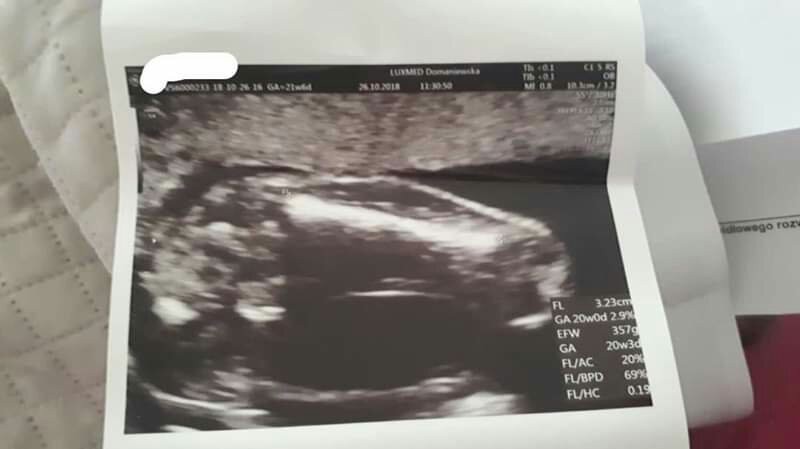

czy to brzuszek , nozki I siusiak ? Mam juz dwoch chlopcow I cicho licze jeszcze na dziewuszke